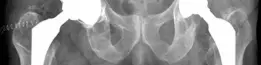

صورة أشعة سينية تظهر مفصل ورك صناعي قد يعاني من تخلخل أو فقدان عظم.

صورة توضيحية لمفصل الورك الصناعي ومكوناته.

صورة توضيحية تظهر فقدان العظم في تجويف الحُق (Paprosky IIIA).